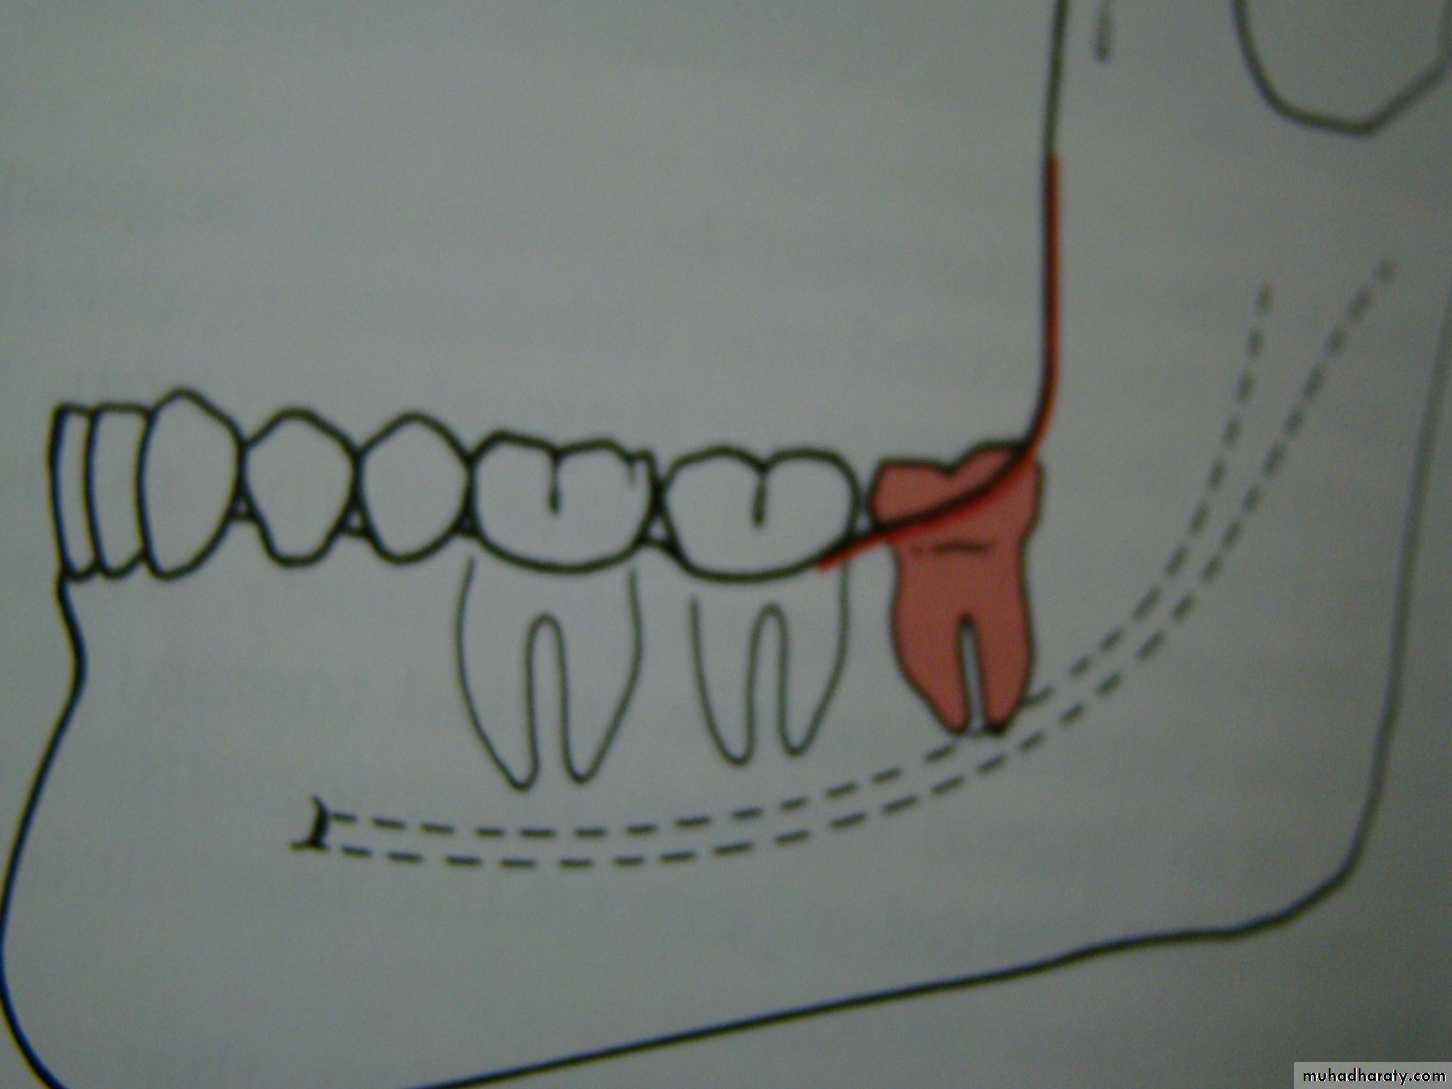

Winters classification of impacted lower third molar

Mesio angularDisto angular

Horizontal

Vertical

Inverted

Transverse

Buccoversion

Linguversion